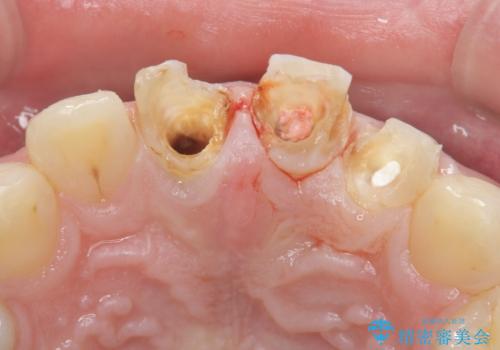

- 前歯の変色や形態を含む、見た目を改善したいと希望され来院されました。

視診・X線検査・歯周組織検査より下記のような問題が列挙され、長期的な予後を見込むために一つづつ問題の解決を計ります。

・不十分な根管治療 →マイクロスコープを用いる精密根管医療

・歯の変色 →ジルコニアクラウンの製作

・歯肉縁下カリエス →部分矯正による歯の挺出・歯周外科